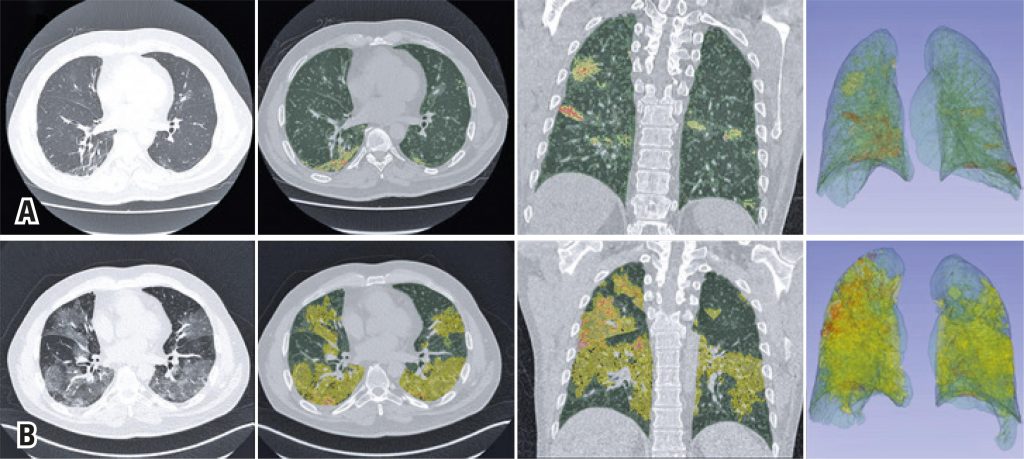

Figure 1

Chest computed tomography and superimposed 3DSlicer software quantification images. The upper series (A) show the findings when the patient returned to the emergency room, and the lower series (B) show the findings at the time of his clinical worsening. Axial sections of the chest tomography showing multifocal pulmonary ground-glass opacities predominantly peripheral and basal, more extensive in the last study, and quantitative images generated by the 3DSlicer software superimposed over the tomographic images. The areas marked in yellow show ground-glass opacities, those marked in green are areas of normal parenchyma, and those marked in orange are areas of consolidation. The extensive progression of the findings illustrates the numerical data provided